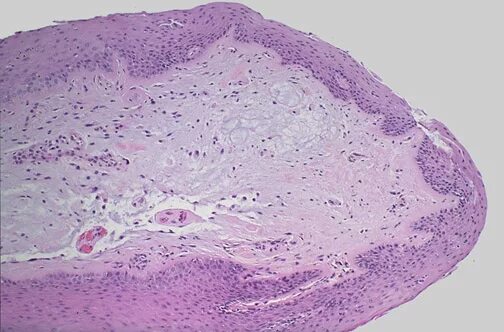

Связки гистология